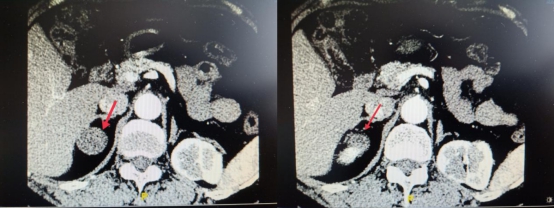

患者出现右上腹疼痛伴恶心呕吐症状,来到ac米兰官网中文网站一院肛肠外科接受治疗,经汪大伟诊断为胆囊结石、胆囊炎、肝内胆管结石及脂肪肝,病犯限期右侧肾上腺区可见一大小约为24mm×20mm,边界清晰的低回声团。请王春阳会诊及进一步检查后,诊断为右侧肾上腺腺瘤。

右侧肾上腺腺瘤